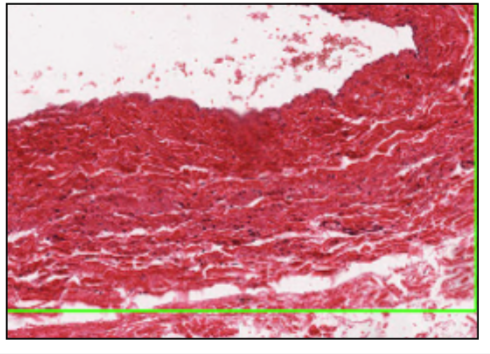

CARDIAC MUSCLE (MYOCARDIUM)

- branching chains of cardiac myocytes

- striations (myofibrils and repeat sarcolemmas)

- dark intercalated discks (myocyte junctions)

differ from skeletal -

- structural - branched, mononuclear (central), no stem cells

- physiological - contract/relax without rest, secrete hormones (ANP- when stretched excessibely, increases water/Na+/K+ excretion, inhibits RAAS)

INTERCALATED DISC

- w/ desmosomes + adherent junctions (stick)

- w/ gap junctions (electrical coupling)

disc = black

myofibrial = blue/black

function:

desmosome - anchor one cardiac muscle to next by immediate cytoskeleton filaments

gap junctions - allow ion transfer between cardiac smooth muscle

electrochemical coupling - not cardiac conduction